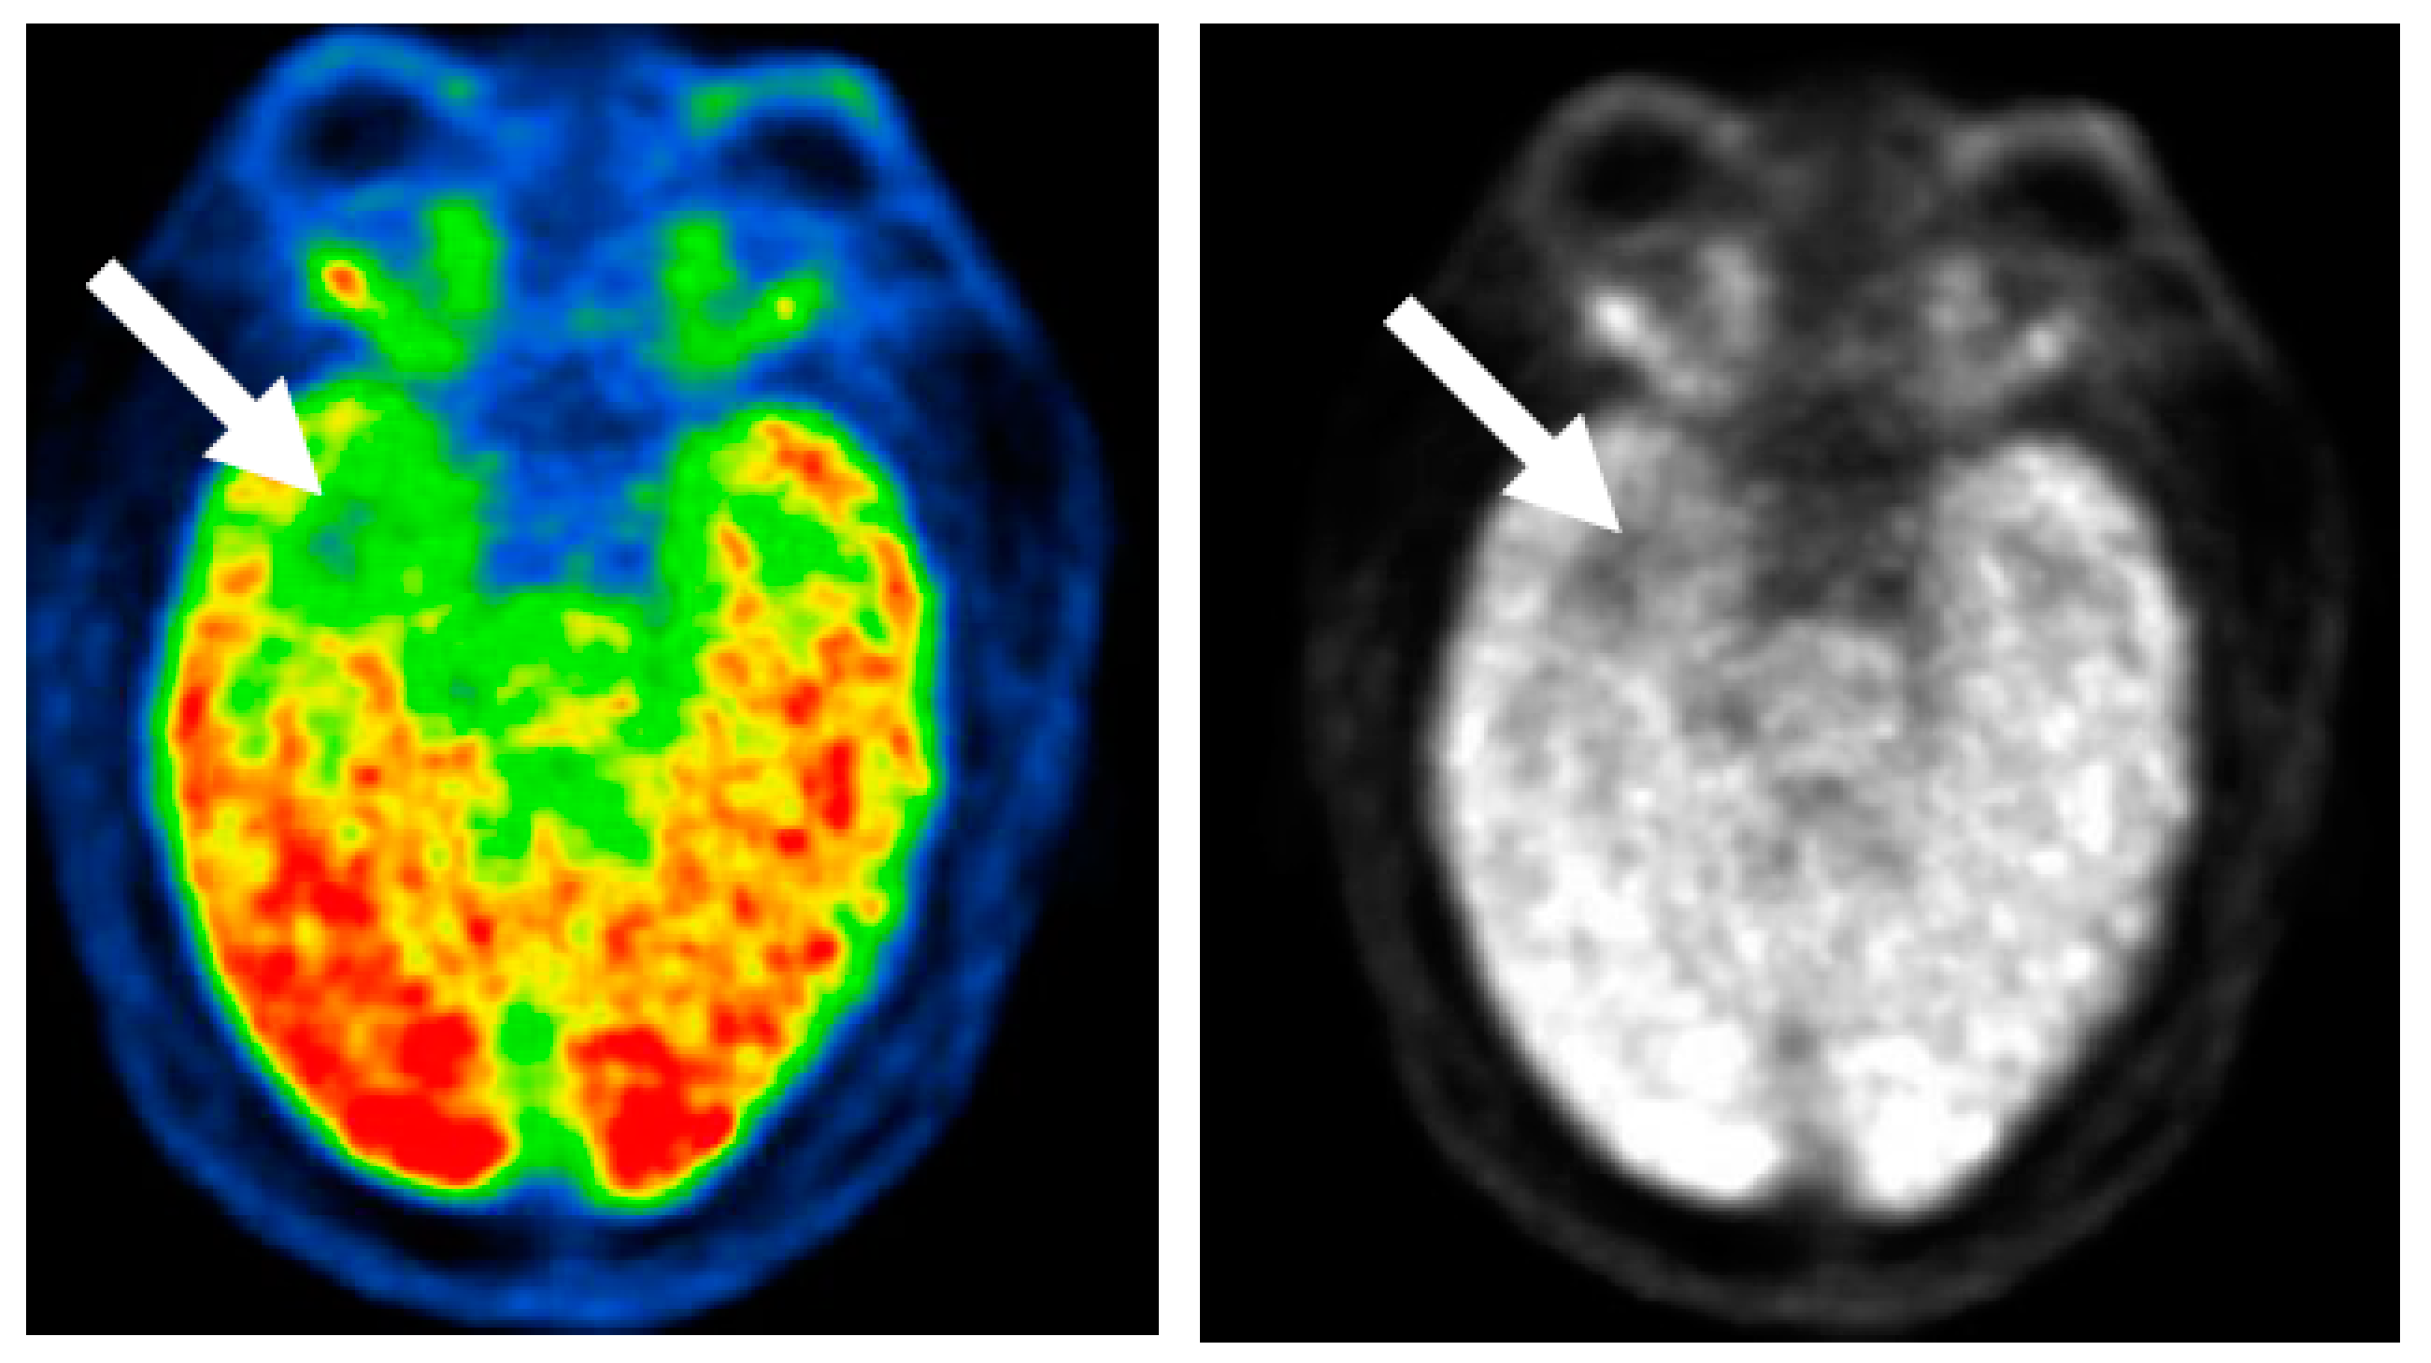

4.2.3. FDG-PET Scan (Fluorodeoxyglucose Positron Emission Tomography)

- Dredla, B.K.; Lucas, J.A.; Wharen, R.E.; Tatum, W.O. Neurocognitive outcome following stereotactic laser ablation in two patients with MRI-/PET+ mTLE. Epilepsy Behav. 2016, 56, 44–47. [Google Scholar] [CrossRef] [PubMed]